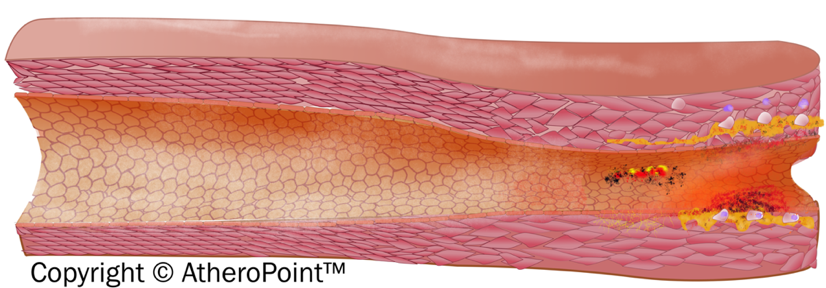

With prolonged exposure to risk factors, it is observed that early fatty streak development begins in childhood and adolescence. Further, early fibroatheroma occurs in the population in their teenage and young adulthood years [101, 102]. Fig. 6 shows the development of an atherosclerotic lesion in the inner lining of an artery.

Fig. 6.

Fig. 6.Development of atherosclerotic lesion.

The initiation of the fatty streak phase of atherosclerosis begins with dysfunctional endothelial cells and the retention of apoB-containing lipoproteins in the sub endothelial space. It is seen that chronic endothelial injury is caused by various factors, including hyperlipidemia, hypertension, smoking, homocysteine, hemodynamic factors, toxins, viruses, or immune reactions. Injury in the endothelial-related region contributes to antithrombotic properties that facilitate the platelet adhesion and activation of the dysfunctional area [10]. The lipoproteins are then modified by the process called oxidation at the extracellular matrix of the subendothelial space [103]. Further, modified LDL promotes the activation of endothelial cells (EC) and smooth cells (SCM) and starts the recruitment of immune cells (i.e, monocytes) into the endothelial layer. These recruited immune cells cause a reduction in nitric oxide inside the endothelial wall resulting in endothelial dysfunction, which further triggers the atherosclerosis process [104]. Collectively, an increased monocyte interaction further differentiates into macrophages and leads to the internalization of VLDL, modified LDL, and apoE remnants. This leads to the formation of foam cells [105].

The foam cells are cholesterol-containing lipid-laden macrophages that lead to the formation of plaque. The endothelial dysfunction begins as atheroma or benign tumors of smooth muscle cells within the blood vessels. It is characterized by increased permeability, leukocyte adhesion, monocyte adhesion, and emigration. Progression of atherosclerotic plaque is seen when numerous macrophage foam cells and other inflammatory cells continue to promote the formation of other monocytes and immune cells.

The proliferation of tunica-media smooth muscle cells leads to the formation of the fibrous fatty lesion [106]. Vaso Vasorum neovascularization exists in atherosclerosis as a compensatory reaction to provide adequate nourishment and oxygen to atherosclerotic arteries [107]. The developing lesions sometimes represent the next stage beyond fatty streaks and are pearly plaque with dome shape appearance often referred to as “cap”. These lesions may further advance and can be represented as calcified fibrous areas of arteries along with visible ulceration [108]. The plaque, which is covered with a thick fibrous cap and has a well matured necrotic core, is referred to as stable plaque. This fibrous cap proves as an effective barrier in preventing plaque rupture and exposure of prothrombin factors in the vascular pathway [109]. An observation of atherosclerosis is that the macrophage cholesterol pathway becomes inefficient, leading to an imbalance in the lipid metabolisms and cholesterol, further progressing to the disruption of cellular functions [110]. Vulnerable plaque is a result of the unresolved and heightened inflammatory status of the lesions of foam cell core. Data reported in a study indicated that some nutritional and toxic trace metals may have a role in the progression or rupture of plaque [111]. Rupture or erosion of the advanced lesion initiates platelet activation and aggregation on the surface of the disrupted atherosclerotic plaque (see Appendix Fig. 13). Thrombotic vascular occlusion is associated with ischemic episodes, including acute coronary syndromes or cerebral infarction [112].